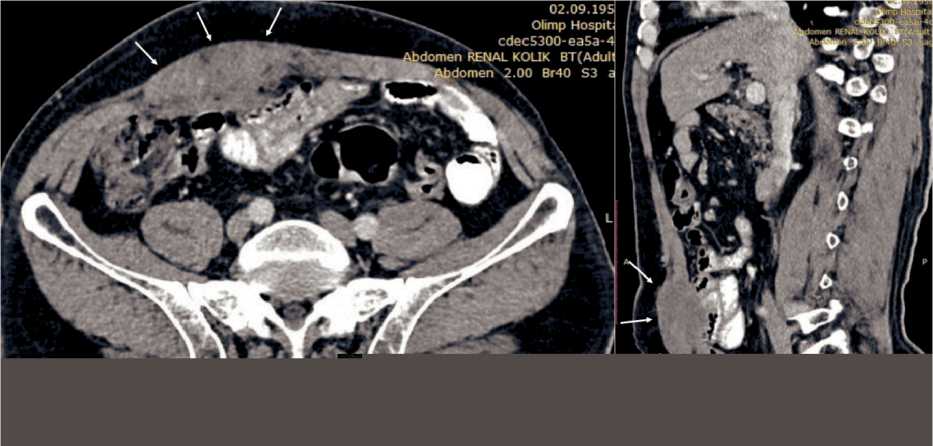

Fifteen years after surgery, the patient returned with a tumor in the anterior abdominal wall. On inspection, a tumor with a long diameter of approximately 10.0 cm was seen in the right half of the anterior abdominal wall, which was mobile on palpation without clinical signs of fixation. On abdominal CT scan, a hypodense tumor measuring 7.0×5.0×4.0 cm was detected in the right rectus sheath without signs of adjacent organ invasion (Fig. 1). Tru-Cut biopsy under US-guidance was conducted. Histopathological examination of biopsy specimen revealed poor-differentiated adenocarcinoma. Taking into the account the tumor histology, all possible primary tumor foci were searched by thoracic and pelvic CT scan, total colonoscopy. No any primary tumor was detected. The tumor was considered to be late metachronous metastasis from gastric carcinoma removed 15 years ago. Wide excision of the tumor with reconstruction of abdominal wall with prolene mesh was planned according to the multidisciplinary team decision.

Fig. 1. CT scan of the tumor in the right rectus abdominis muscle (arrows). A – axial slice; B – sagittal slice. Note: created by the authors Рис. 1. КТ опухоли в правой прямой мышце живота (указана стрелками). А – аксиальный срез; Б – сагиттальный срез. Примечание: рисунок выполнен авторами